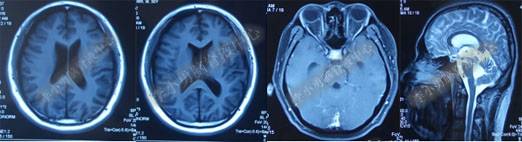

术后7天(2016年5月18日),症状有所缓解,复查头部MRI(图-2)幕上脑室较术前缩小,但是“四脑室仍扩张”,医生认为 “正常”于术后8天(2016年5月19日)出院。

图-2:2016年5月18日头部MRI

图-3:2016年9月26日头部MRI

第1次内镜术后330余天即11个月(2017年4月),又开始出现头晕症状并逐渐加重。2017年6月13日(第1次内镜术后367天),行头部MRI(图-4)检查显示全脑室系统扩大。

图-4:2017年6月13日头部MRI